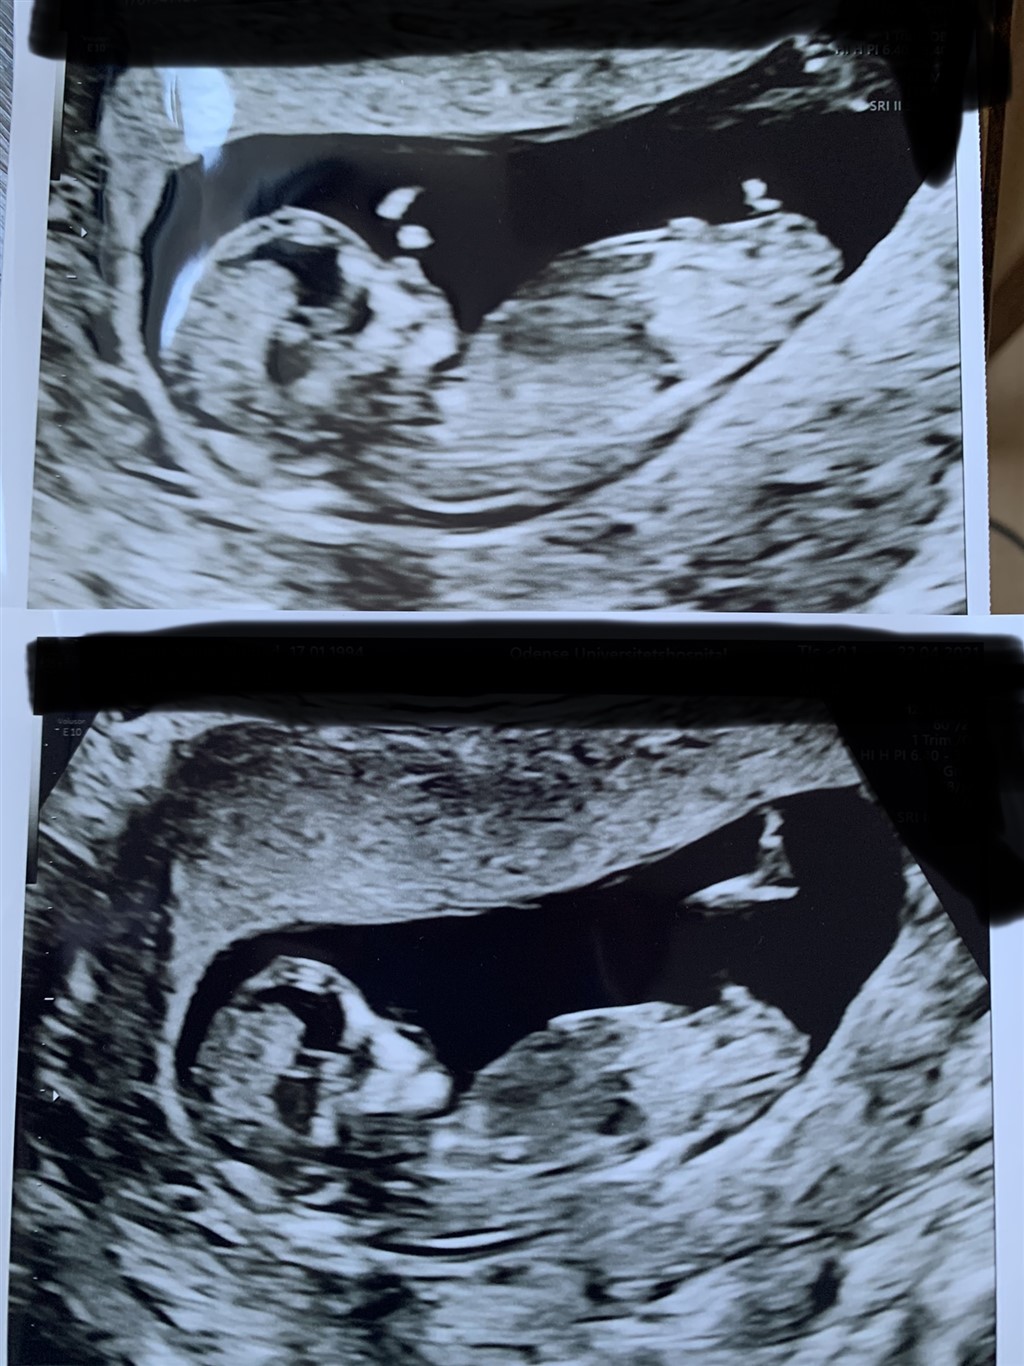

Simoneandthebaby

Nogen der vil gætte hvad det ligger i min mave?

Vedhæftede fotos (klik for at se i fuld størrelse)